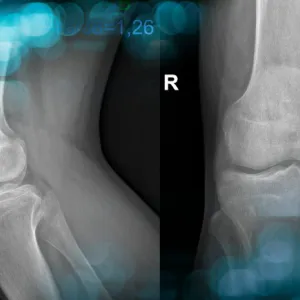

Discover the case of a 58-year-old man with a history of high tibial osteotomy, osteitis, and medial collateral ligament insufficiency, who underwent a total knee arthroplasty and experienced complications 6 months post-op. What kind of complication did the surgical team face, and how did they manage it?